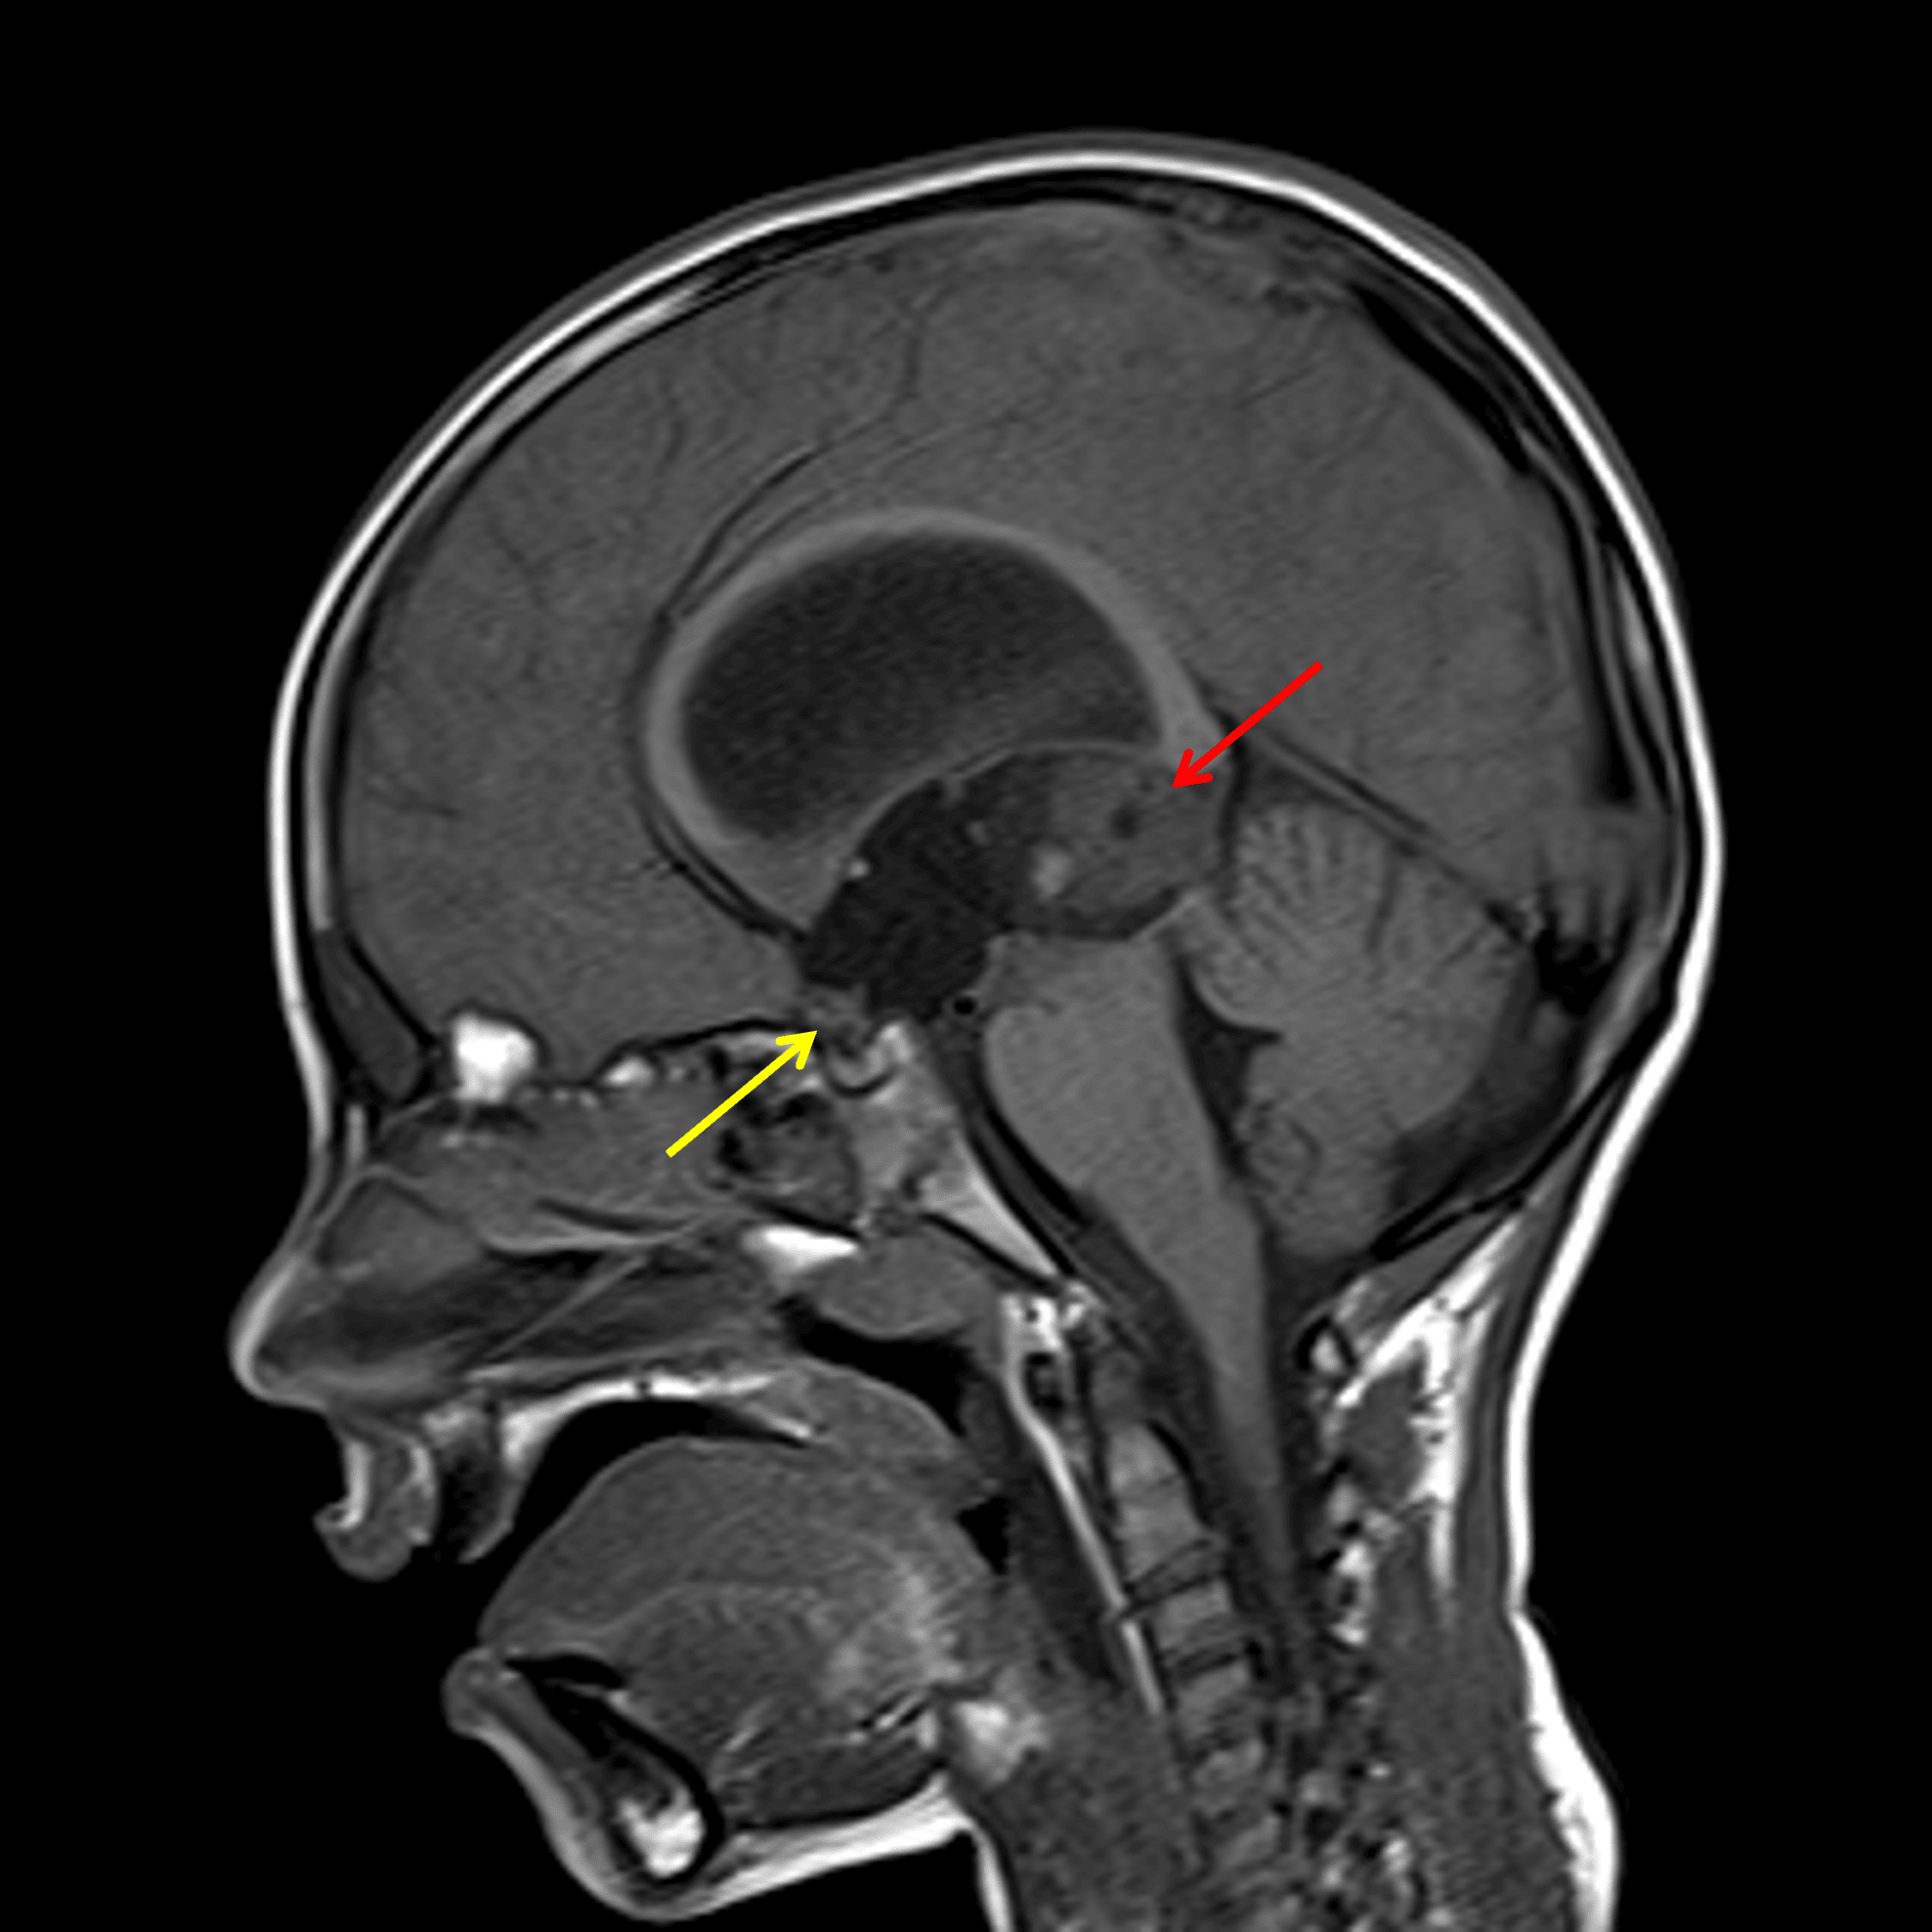

Dominant mass in the pineal region (red arrow) with a smaller mass anteriorly centered in the anterior recesses of the third ventricle (yellow arrow).

• Heterogeneous pineal region mass measuring 2.4 x 2.3 x 2.3 cm which bulges into the posterior aspect of the third ventricle and exerts downward mass effect on the tectum with obstruction of the cerebral aqueduct

• Additional site of abnormal soft tissue centered in the chiasmatic and infundibular recesses of the third ventricle, which may represent a separate tumor or intraventricular tumor spread

• Obstructive hydrocephalus involving the lateral and third ventricles with subependymal edema